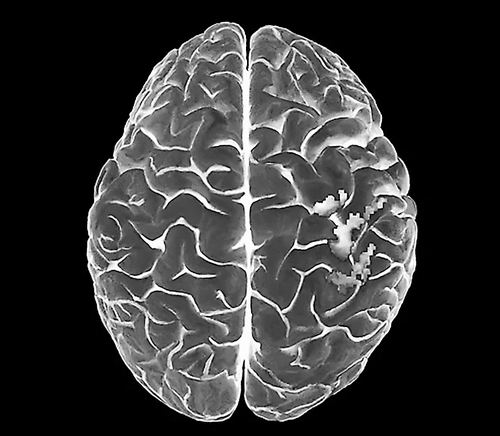

截肢后,大脑初级体感皮层中的躯体图谱保持不变。图片来源:Zephyr

本报讯 一项针对截肢者的脑成像研究发现,大脑中的“身体地图”并不会因为身体部位的缺失而自我重组。这颠覆了长期以来的科学共识。8月21日,科学家在《自然-神经科学》上发表了这一研究成果。

此前的研究认为,负责处理躯体感觉的初级体感皮层神经元,会生长到之前负责感知截肢体的皮层的邻近区域。但最新研究结果表明,即使在截肢多年后,初级体感皮层也保持着非常稳定的状态。研究人员表示,这一发现颠覆了神经科学领域的基础知识,即失去肢体会导致该区域神经重组。此外,该发现有助开发更先进的假肢设备、改善幻肢痛治疗,并帮助科学家找到恢复截肢者感觉功能的方法。

结果发现,即便在截肢5年后,缺失手部对应的皮层映射区仍像术前一样被激活。此外,没有证据表明相邻唇部感知脑区如传统理论预测的那样转移到手部区域。Makin表示,这是证明大脑内置躯体图谱具有稳定性的“最具决定性的直接证据”。